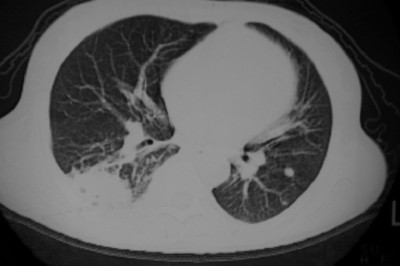

以下是引用天南地北在2007-4-10 1:49:00的发言:[br]考虑右下叶周围型肺癌伴肋骨转移。

以下是引用jone-baby在2007-4-10 8:45:00的发言:[br][br] [br] 患者[br]有发热史,x线片考虑肺脓肿.肺脓肿可以导致肋骨破坏吗?[br]脓肿可以排除吗? [br] [br] [br]

以下是引用林建春在2007-4-10 7:35:00的发言:[br]周围型肺癌侵犯肋骨

以下是引用liuyue在2007-4-10 7:56:00的发言:[br]周围型肺癌侵犯肋骨,左肺转移。

以下是引用zhangzhongshou在2007-4-10 10:24:00的发言:[br]右肺下叶背段厚壁空洞,伴胸膜改变、肋骨破坏,其内可见死骨、周围骨质硬化,左肺可见小结节影,[br]单纯影像学更支持结核。建议进一步检查。